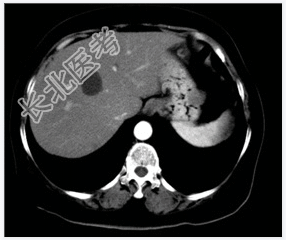

- [材料题] 患者,女性,40岁。体检B超发现肝内囊性病变,行上腹部CT增强扫描。

- 简答题1、患者的诊断及依据是什么?

- 简答题2、鉴别诊断有哪些?